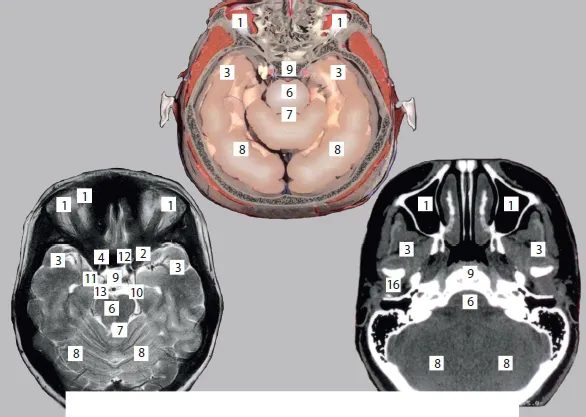

This comprehensive and exhaustive medical atlas of topographic and pathotopographic human anatomy is a fundamental and practically important book designed for doctors of all specializations and students of medical schools. Here you can find almost everything that is connected with the topographic and pathotopographic human anatomy, including original graphs of logical structures of topographic anatomy and development of congenital abnormalities, topography of different areas in layers, pathotopography, computer and magnetic resonance imaging (MRI) of topographic and pathotopographic anatomy. You can also find here new theoretical and practical sections of topographic anatomy developed by the author himself which are published for the first time. They are practically important for mastering the technique of operative interventions and denying possibility of iatrogenic complications during operations.

Topography and Pathotopography of the Head